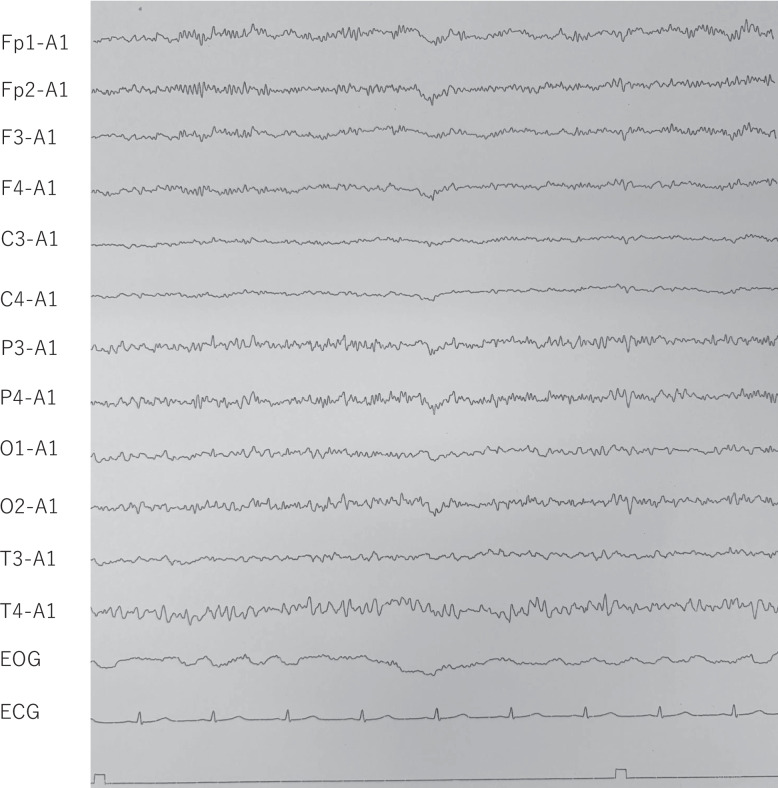

Case presentation: We report five cases of catatonia (including malignant catatonia) associated with schizophrenia or schizoaffective disorder. These cases were treated either in a psychiatric hospital or an outpatient clinic, both of which lacked access to ECT. Extended-release formulation of guanfacine was administered alongside temporary benzodiazepine use, and treatment outcomes were observed. All five patients were in syndromal remission from catatonia following treatment that included guanfacine in combination with other pharmacological interventions. Mild to moderate side effects were observed. These included dizziness and fatigue in one patient, and hypotension and bradycardia in two others. All adverse effects resolved with dose reduction. Complications of catatonia included impaired oral intake requiring nutritional support in two patients and urinary catheterization due to immobility in two patients.

Conclusions: These findings suggest that guanfacine may serve as a safe and effective alternative to ECT for catatonia in settings where ECT is unavailable or relatively contraindicated. The clinical courses also suggest that dysfunction of the central noradrenergic system may contribute to the pathophysiology of catatonia, and that guanfacine's selective α2A adrenoceptor modulation may play a role in symptom improvement. Further research is needed to validate these findings and clarify the underlying mechanisms.